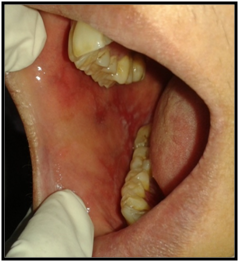

On intraoral examination, diffuse lesions in the form of erythematous areas were seen interspersed within white keratotic areas present all over the facial aspect of gingiva (Figure 2) and more posteriorly on the buccal mucosae bilaterally (Figure 3). Left buccal mucosa showed a white erythematous patch measuring approximately 2x2.5cms extending anteroposteriorly from the area adjacent to mandibular first molar to the retro molar pad area and superior inferiorly from the line of occlusion to the upper and lower lingual vestibule. White radiating striae (wickhamstriae) were present with an interspersed erythematous patch. Right buccal mucosa showed a more extensive lesion measuring approximately 2.5x3cms extending anteroposteriorly from the region adjacent to mandibular canine to the retromolar pad area and superioinferiorly from the upper gingiva buccal sulcus to the lower gingivobuccal sulcus and the alveolar mucosa. Borders of the lesion appear irregular and ill defined. On palpation, the lesions appeared to be tender. The surface of the lesions were rough and non scrapable with no induration noted.

Figure 2The Lesion on the Right and Left Buccal Mucosae.